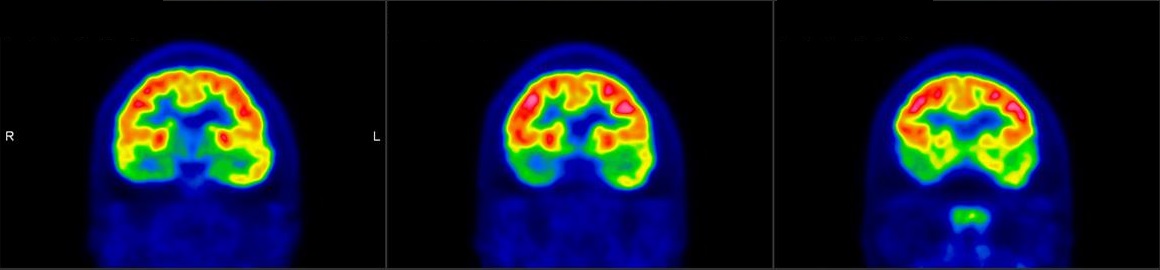

脑神经科

![]() [C-11] PIB |

![]() [C-11] Raclopride |

![]() [F-18] DOPA |

脑神经疾病